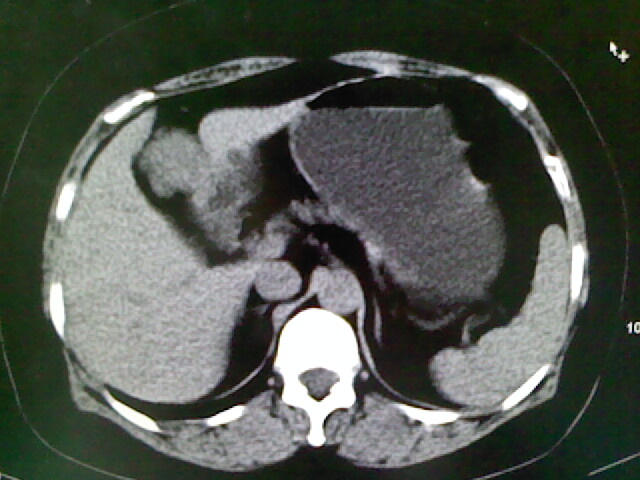

以下是引用卜一在2009-4-2 13:26:00的发言:[br]胆囊颈部结石伴胆囊炎!另:建议增强,待除外肝内占位及胆囊占位!

以下是引用liaoqiang在2009-4-2 16:23:00的发言:[br]胆囊是否切除?胆囊颈区致密影考虑金属夹?结石?肝脏右叶低密度影,考虑增强。